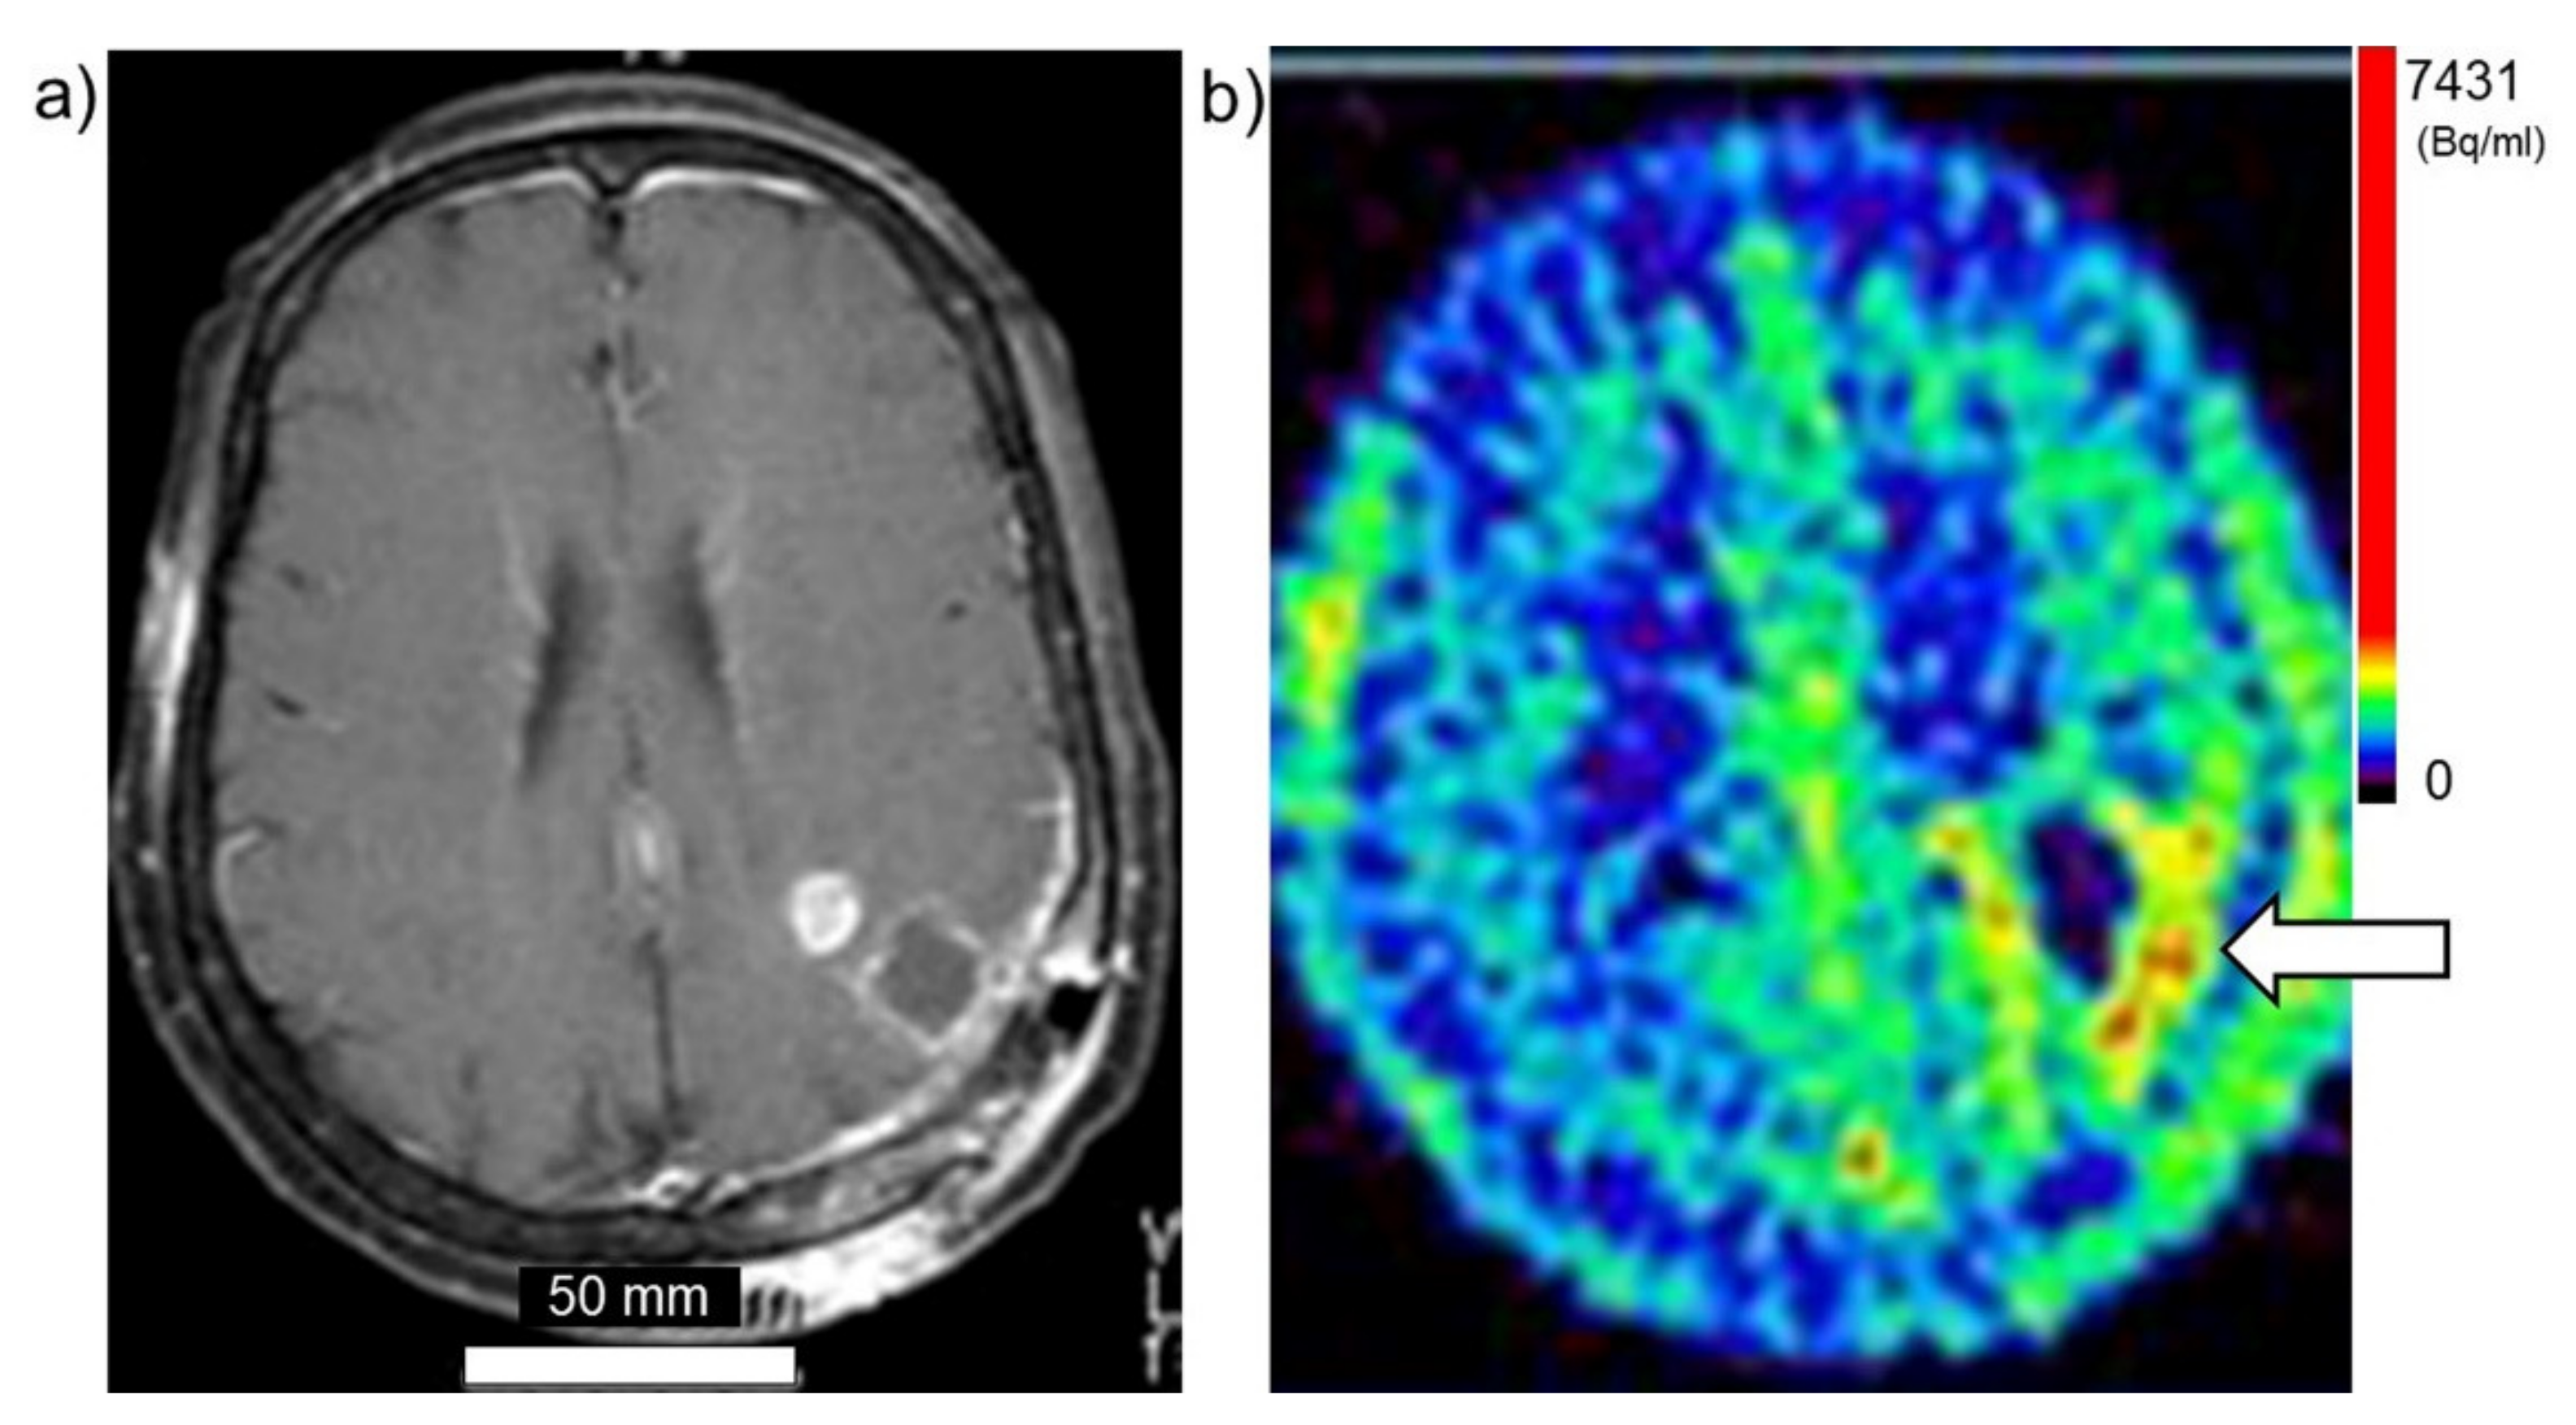

Taken together, these findings suggest that PET using 18FBPA is a useful and reliable treatment strategy for BNCT that is mainly used for determining the treatment indications, predicting the distribution of the 10B in the tumor and surrounding normal tissues, and enabling high-precision treatment planning. Figure 3a,b show brain tumor. Gadolinium enhanced lesion is found in the left parieto-occipital lobe, and abnormal accumulation is also found in 18FBPA PET. Figure 4a,b show tongue cancer. Huge tumor with high 18FBPA accumulation is seen in the floor of the right oral cavity and reaches the mandible. Figure 5a,b show melanoma. Abnormal accumulation is seen in the right neck.

Figure 3. Brain tumor (glioblastoma). (a) MRI, (b) 18FBPA PET. Arrow presents tumor lesion. Accumulation is shown in rainbow-color scale (high in red and low in blue).